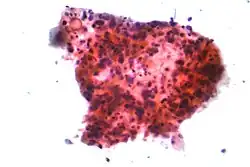

Karcinomy plic jsou klasifikovány podle histologického typu.[11] Tato klasifikace je důležitá pro určení způsobu léčby a předvídání dalšího vývoje nemoci. V naprosté většině případů rakoviny plic se jedná o karcinomy – zhoubné bujení buněk epitelové tkáně. Karcinomy plic se rozdělují do kategorií podle velikosti a vzhledu buněk zhoubné tkáně tak, jak ji pod mikroskopem vidí histopatolog. Dvěma hlavními skupinami jsou nemalobuněčné a malobuněčné karcinomy plic.[59]

_by_core_needle_biopsy.jpg)

V případě malobuněčných karcinomů plic (SCLC) buňky obsahují kompaktní neurosekreční granula (váčky naplněné neuroendokrinními hormony), které by u tohoto tumoru mohly naznačovat souvislost s endokrinním/paraneoplastickým syndromem.[62] Ve většině případů se karcinomy objevují ve velkých cestách dýchacích (primární a sekundární průdušky).[13] Tyto typy karcinomu rychle rostou a šíří se již v rané fázi onemocnění. V šedesáti až sedmdesáti procentech případů u nich dochází k metastázím. Tento typ rakoviny plic velmi významně souvisí s kouřením.[1]